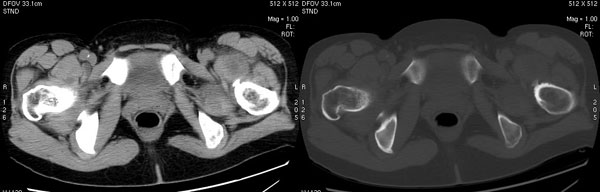

以下是引用jiajie在2006-7-14 17:19:00的发言:[br]ct所见:双侧髋关节不对称,左侧关节间隙变窄,关节面毛糙。左侧股骨头变形、无明显变小,前上缘与髋臼融合,融合处骨质明显增生硬化,并见数个小囊变影。股骨头下端与股骨颈交界部见囊样变,邻近肌肉内见囊样密度减低区,ct值24hu。右侧髋关节形态未见异常。[br][br]ct诊断:左侧髋关节结核可能,请结合临床资料进一步分析。

以下是引用lihuuuu在2006-12-5 10:14:00的发言:[br]定位像示:左侧髋臼变浅,倾斜度加大,髋臼外上缘呈波浪状不规则,骨质增生硬化,髋关节上缘间隙明显变窄,股骨头向外上轻度移位。轴位像示:左侧股骨头变形,前上缘与髋臼融合,融合处骨质明显增生硬化,并见数个小囊变影。股骨头下端与股骨颈交界部见囊样变,邻近肌肉内见密度减低区,ct值24hu,内缘见弧形高密度钙化影。右侧髋关节形态未见异常。[br]ct诊断:左侧髋臼发育不良[br] 左侧股骨头缺血性坏死[br] 左侧肌肉内低密度影伴有高密度钙化-考虑早期骨化性肌炎[br] [br]“我认为在描述上已经写了肌肉部分,印象诊断里应该写主见”[br]